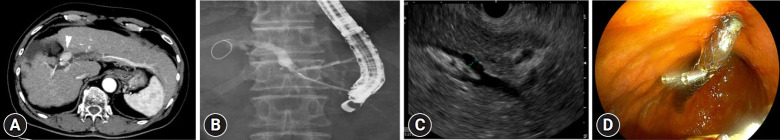

Results: A total of 14 EUS-HGS procedures (42.9% primary) were attempted in 10 HCC patients (mean age 71.5 years, 80.0% male). Clinical and technical success rates were 92.9% and 90.9%, respectively. The observed procedure details in the 13 successful procedures included B3 puncture (53.8%), 22-G needle (53.8%), fully covered self-expandable metal stent (100%), and mean procedure time (32.7 minutes). There was no bleeding. Mild complications occurred in 27.3%. All patients resumed oral intake within 24 hours.

Conclusions: EUS-HGS is a technically feasible and clinically effective initial or salvage drainage option for the treatment of biliary obstruction in patients with HCC.